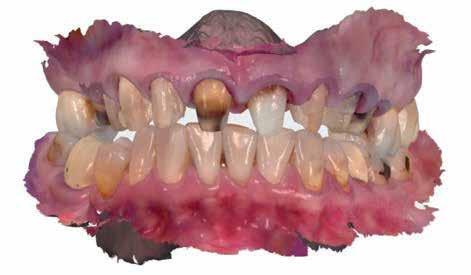

A rendelésünkön jelentkező 40 éves nőbeteg a mosolyának esztétikai megjelenésén szeretett volna javítani (1. ábra)

A vizsgálat során a jobb felső első kisőrlőfog (1,4) és a bal felső első kisőrlőfog (2.4), valamint a köztük elhelyezkedő fogak kifejezett mértékű kopását észleltük (14-24). Ezen felül a felső metszőfogak (1.2–2.2) élei egyenetlen lefutással rendelkeztek, és a jobb felső nagymetszőfog (11) – amelyet korábban gyökérkezeltek és kompozit töméssel láttak el –jelentős színbeli eltérést mutatott. Az 1.4-es és 2.4-es fo-

A jelen cikkben bemutatásra kerülő eset ellátása során az esztétikai zóna kezelése minimál invazív megközelítéssel történt. A kezelések megkezdése előtt a páciens két fő panaszt említett: a fogai között látható rések, valamint az elszíneződött jobb felső nagymetszőfoga zavarta leginkább.

A 26 éves férfi páciens azzal a kéréssel kereste fel a rendelőnket, hogy a frontfogai esztétikusabb megjelenését szeretné elérni. A páciens jó általános egészségi állapottal rendelkezett, nem szenvedett allergiáktól és nem kellett rendszeresen gyógyszereket szednie. A páciens lehetőség szerint kerülte a fogai megmutatását. Rendkívül zavarónak találta a nagymetszői között, a középvonalnak megfelelően látható rést, a fogain látható kopási jeleket, valamint a fogai méretét is túl kicsinek találta. A szájüregi vizsgálat során megállapítottuk, hogy a nagymetsző fogai (11, 21) élharapásban vannak, valamint az alsó fogíven kismértékű torlódást észleltünk. A felső frontfogakon

(13-23) attrícióra utaló jeleket találtunk. A fogak kopása a nagymetszőfogaknak megfelelően volt a legkifejezettebb (1. ábra) . Az előbbiekben említett fogak (11, 21) ezen kívül némileg elfordultak, és jelentősebb méretű diasztéma volt köztük. A páciens Angle I.-osztályú állcsontrelációs helyzettel rendelkezett. A vizsgálat során feltűnt, hogy a páciens csak nagyon óvatosan mert mosolyogni (2. ábra)